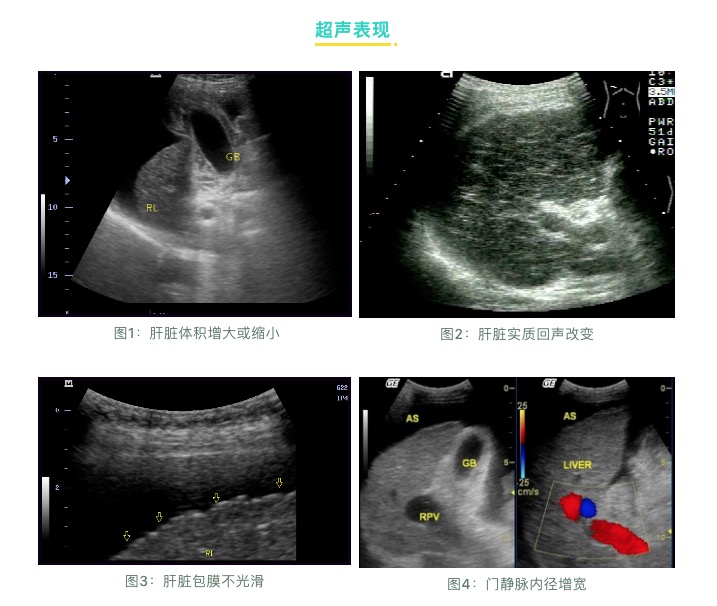

超聲檢查:

肝臟受病毒感染和發(fā)生炎癥后,就會造成肝臟內(nèi)部的結(jié)構(gòu)損傷,從局部的纖維化、結(jié)節(jié)性肝硬化到最后的全面硬化,超聲檢查是早期發(fā)現(xiàn)肝硬化的最直接指標(biāo)。